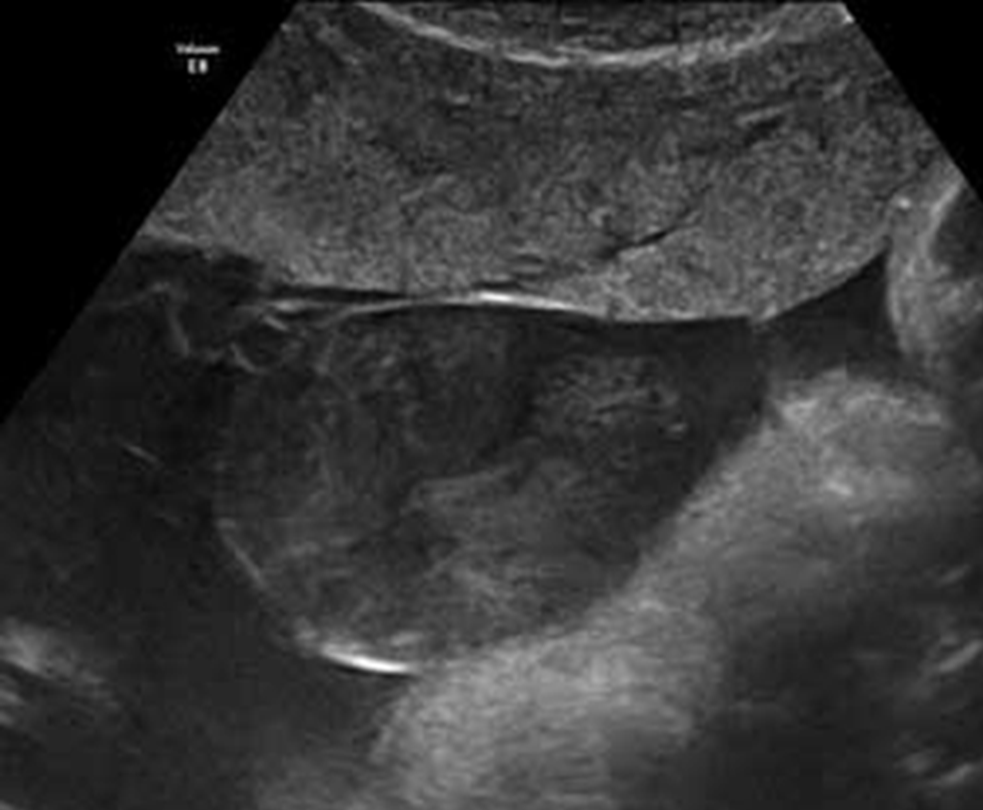

Abb. 1: subamniales Hämaton

Abb. 2: Subamniales Hämatom

Abb. 5: SubamnialesHämatom